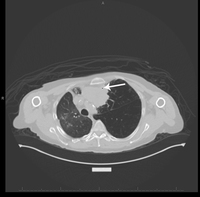

Figure 1: PET and CT Scans in Plasmacytoma-Like PTLD, EBV+

The image on the top left shows hypermetabolic foci within the abdomen corresponding to multiple bowel loops. In addition, there were several hypermetabolic foci within the abdominal wall, right pelvis, and left lower pelvis.

The image on the top right shows hypermetabolic anterior mediastinal conglomerate lymph node mass with central necrosis.

The CT at the bottom left additionally shows the mediastinal involvement.